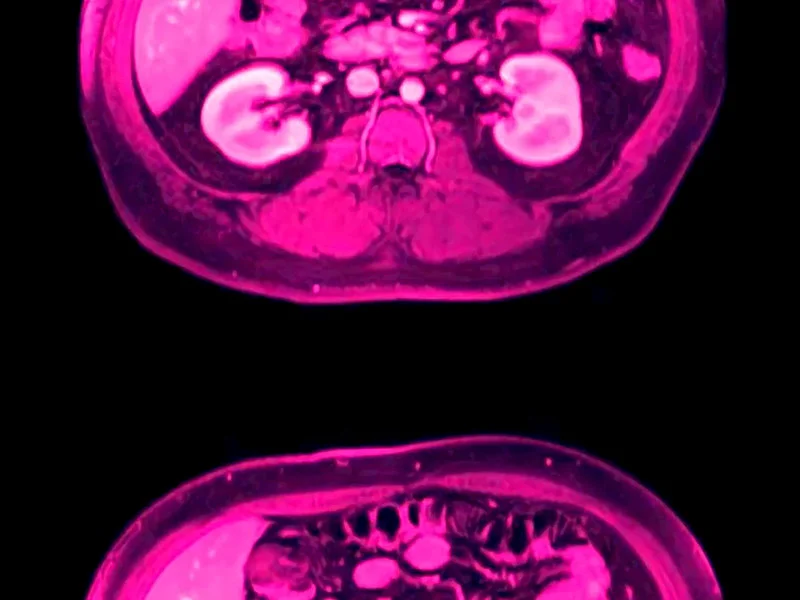

in ocula oculorum interrogates the unknown and the internal, in both subject matter and experience. Dealing with the contemporary state of perpetual doom, the film contemplates various stages of life and death from the point of view of our human bodies and perceptual systems. It explores beta movement and phi phenomenon, pushing the limits of intermittence and persistence of vision, playing with our innate desire for continuity and cohesion by forcing image slip.